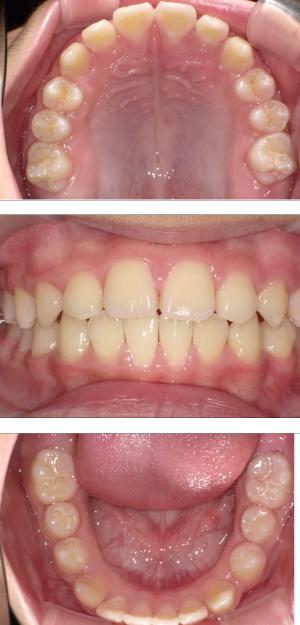

矯正治療は大人になって始めるよりも子どもの頃から始めた方が確実に良い結果をもたらします。成長が盛んな子供の時期に、顎や顔の成長を利用しながら治療ができる大きなメリットがあるからです。当院では、非抜歯矯正を推奨しておりバイオブロック矯正を取り入れています。

バイオブロック矯正の考え方は歯並びが悪くなる原因にアプローチする治療法になります。

舌の位置や口呼吸から乱れてしまった下顎の後退を正し、顎顔面が本来あるべき位置へと誘導させていく治療です。

- 歯並びの改善

- 歯を動かすのではなく顎の成長を促す

- 非抜歯矯正ができる

- 側方拡大だけでなく前方成長も促す

- お顔の成長が正しく美しく導くことができる